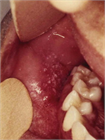

1. 臨床診断が重要である(潜伏期間、Koplik斑、カタル期後に全身に広がる発疹の出現)。